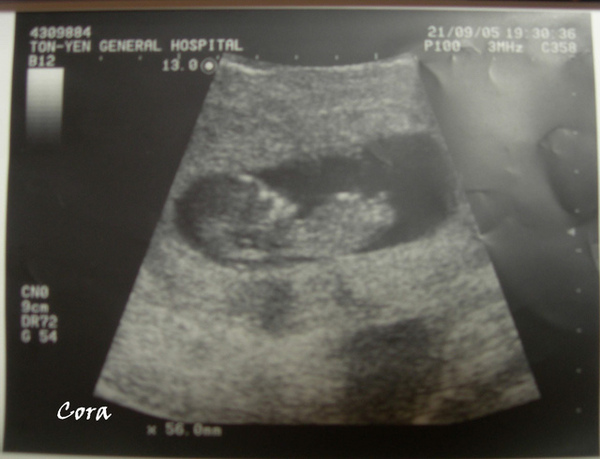

不過看到一個小小人在肚子裡手足舞蹈還是覺得很神奇,一直覺得自己懷孕是個錯覺,原來他還是真真實實的在長大,還是覺得很感動,比起不認真的媽,他可認真多了~

預產期在明年四月,到時候我就變二個孩子的媽了,想想還真惶恐...